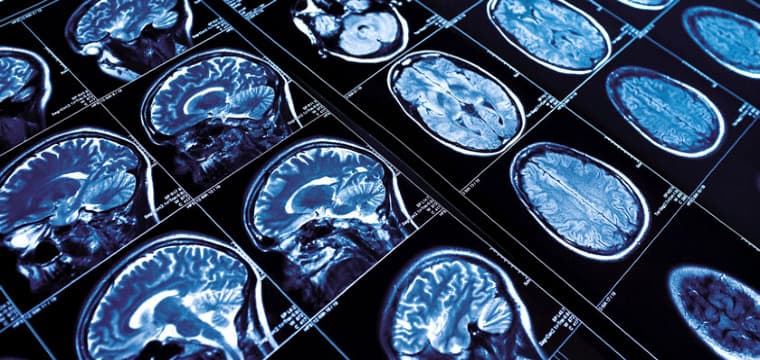

Advanced imaging techniques play a crucial role in diagnosing cerebrovascular disease. One of the most commonly used imaging methods is computed tomography (CT) scanning, which provides detailed cross-sectional images of the brain, helping to identify areas of bleeding, infarction (tissue death due to lack of blood flow), or other abnormalities. Magnetic resonance imaging (MRI) is another powerful tool that offers high-resolution images of brain structures and can detect early signs of cerebrovascular disease, such as small strokes or transient ischemic attacks (TIAs).